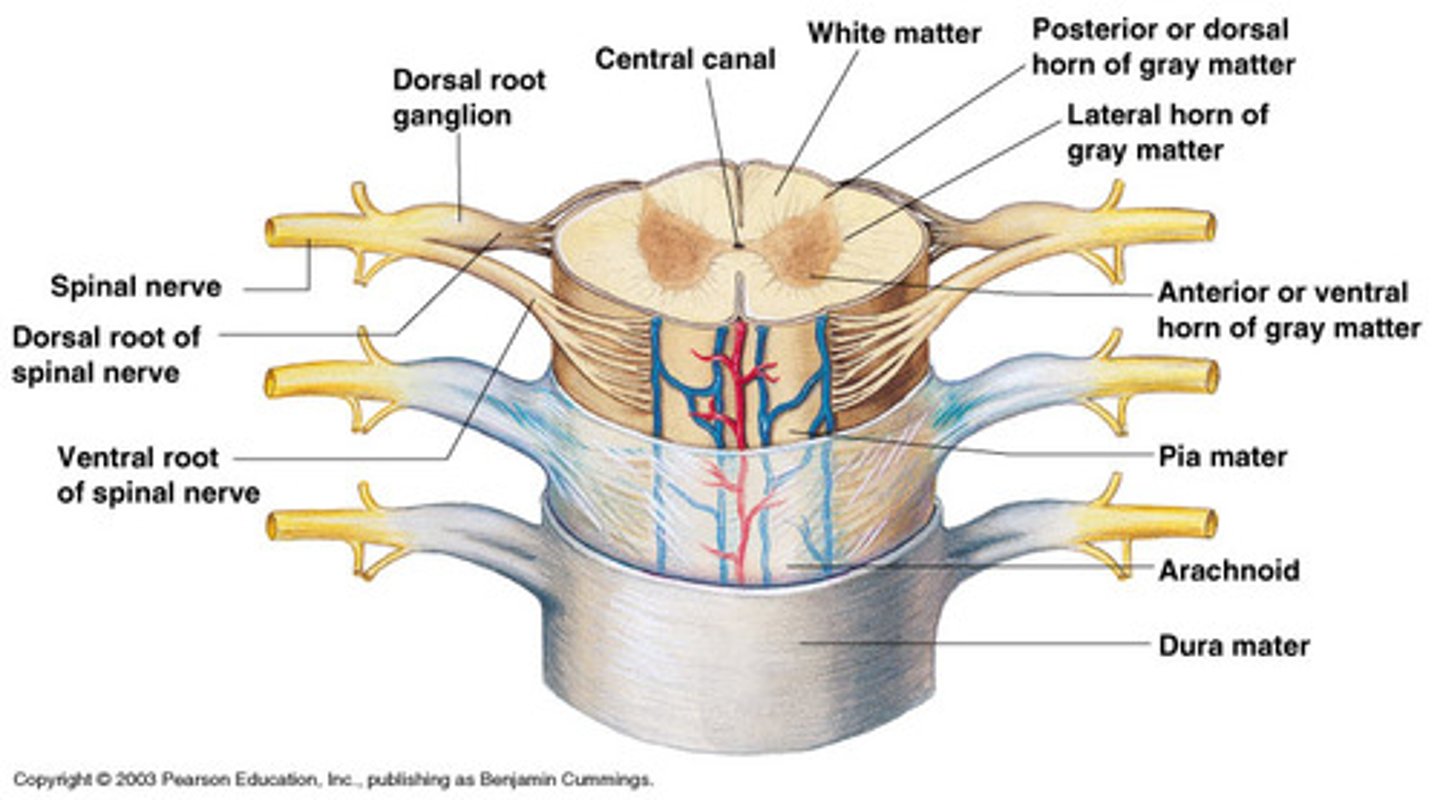

Spinal cord Anatomy (cross-sectional)

1)Internal butterfly shaped gray matter,

2)Exterior white matter,

3)Central canal filled with cerebrospinal fluid (CSF),

4)Cushioned & protected by meninges,

5)Pia mater,

6)Spinal nerves leave at the level of each vertenrae

Horns of Spinal Cord Anatomy

Dorsal Horns,

Ventral Horns,

Lateral Horns

Dorsal Horns

Lateral Horns

Ventral Horns

Interneurons

exterior white matter of the spinal cord

Ascending (sensory) and descending (motor) myelinated nerve tracts,

Posterior, anterior, lateral columns or funiculi

Posterior Columns

Anterior Columns

Lateral Columns/ funiculi

Central canal filled with what?

Central canal filled with cerebrospinal fluid (CSF)

Cushioned and protected by meninges

1) Cover the spinal cord

2) Dura mater, Arachnoid & Pia mater

dura mater of spinal cord

1) Separated from the periosteum by the epidermal space (fat, blood vessels)

2) Subdural space between dura and arachnoid mater

Dura Mater